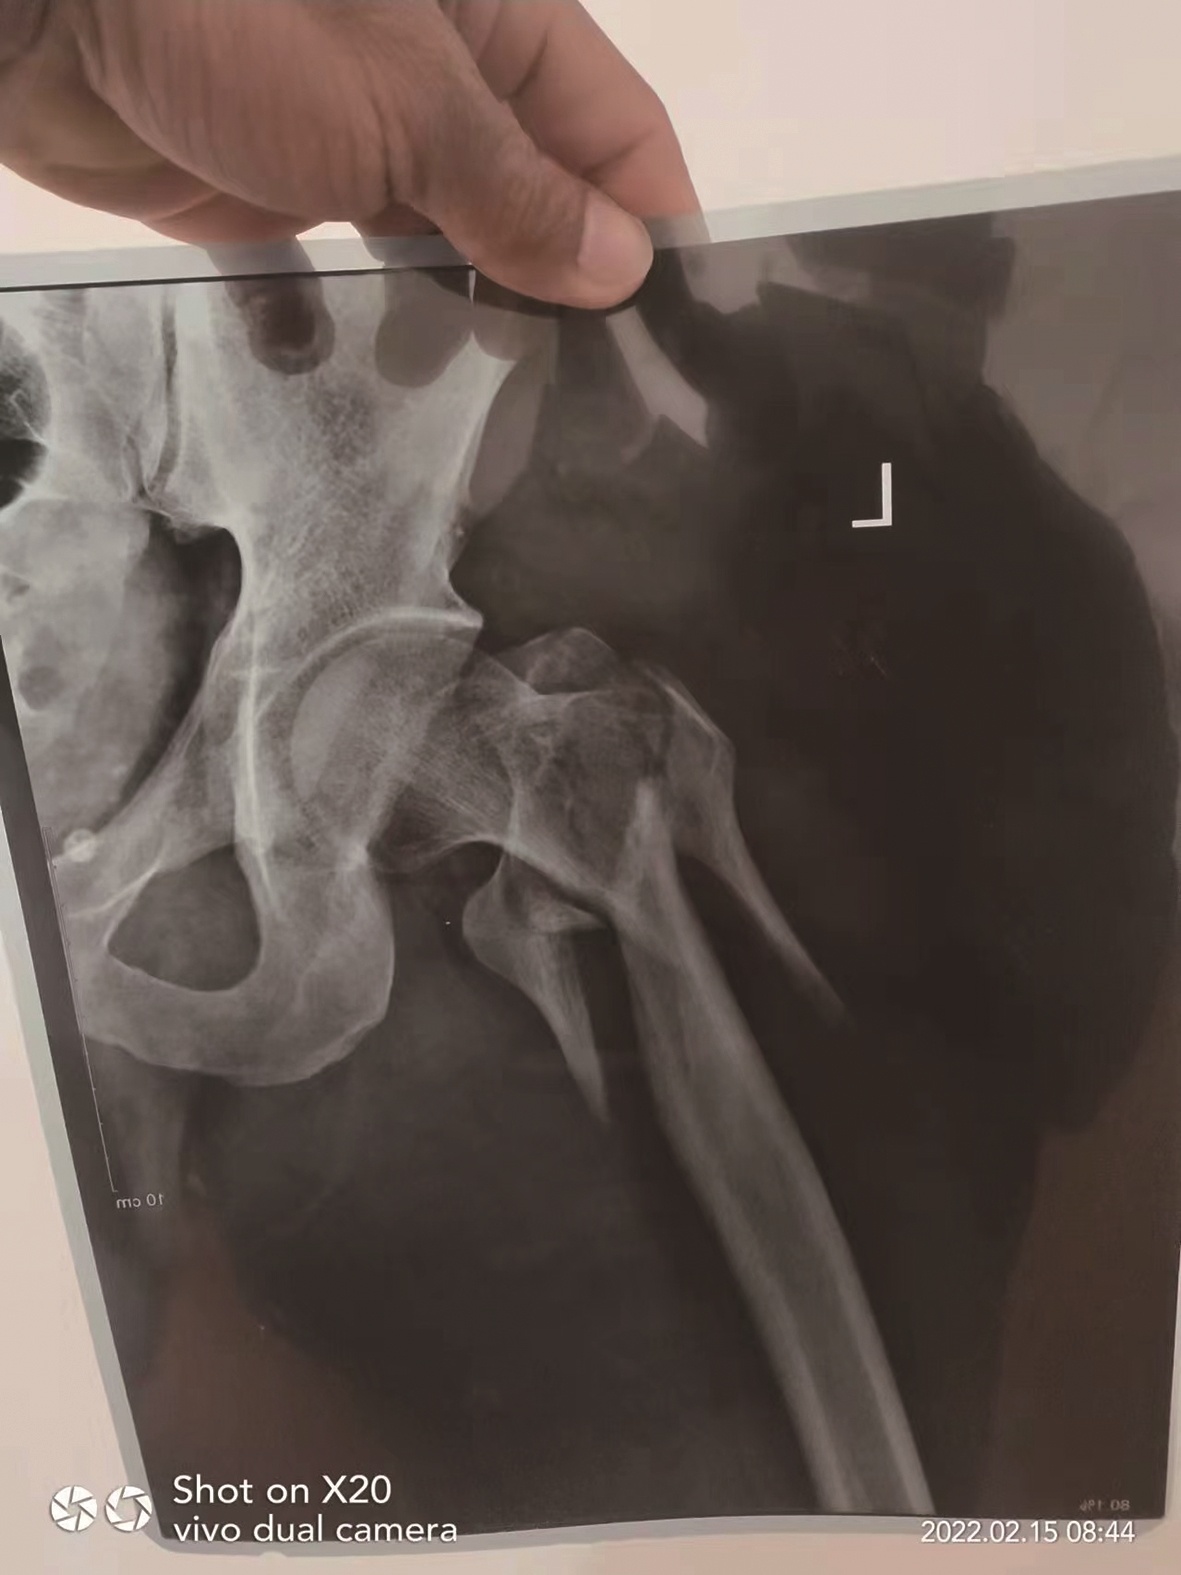

“只要不听话,就会被毒打。”小许说因不想从事犯罪行为,自己无数次萌生过逃跑的念头。2021年6月底,他从公司4楼一跃而下摔成骨折,目前仍在当地医院治疗。欧阳却没有这么好运,他从楼上跳下后被公司的人发现,目前人身自由仍然受限。

相比小许,欧阳的情况更为糟糕。在跳楼逃生后,欧阳并未逃离公司的魔爪。欧阳告诉记者,自己跳楼后被公司的人送到医院治疗,其家人已支付了医疗费。目前,他仍在公司外籍人员的监视下,只得通过手机向外求助。虽已看淡了生死,但仍希望可以回国,“我希望用亲身经历告诉大家,不要轻信有高薪工作,来东南亚工作需要三思后行。”欧阳称。